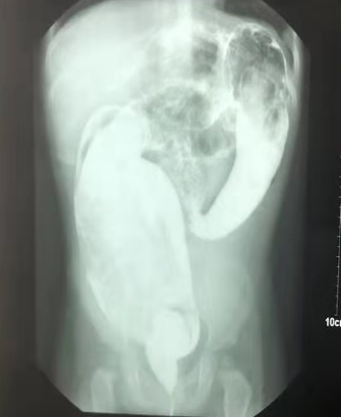

undefined

上图为先天性巨结肠行造影检查,显示近端扩张的肠管